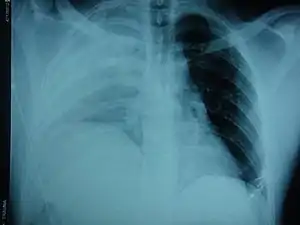

| An X-ray showing a raised diaphragm on the right[1] | |

Physical examinations are not accurate, as there is usually no specific physical sign that can be used to diagnose this condition.[3] Thoracoscopic and laparoscopic methods can be accurate.[12] Chest X-ray is known to be unreliable in diagnosing diaphragmatic rupture;[4] it has low sensitivity and specificity for the injury.[5] Often another injury such as pulmonary contusion masks the injury on the X-ray film.[6] Half the time, initial X-rays are normal; in most of those that are not, hemothorax or pneumothorax is present.[4] A nasogastric tube from the stomach may appear on the film in the chest cavity; this sign is pathognomonic for diaphragmatic rupture, but it is rare.[4] The X-ray is better able to detect the injury when taken from the back with the person upright, but this is not usually possible because the person is usually not stable enough; thus it is usually taken from the front with the person lying supine.[5] Positive pressure ventilation helps keep the abdominal organs from herniating into the chest cavity, but this also can prevent the injury from being discovered on an X-ray.[4]

Between 50 and 80% of diaphragmatic ruptures occur on the left side.[5] It is possible that the liver, which is situated in the right upper quadrant of the abdomen, cushions the diaphragm.[6] However, injuries occurring on the left side are also easier to detect in X-ray films.[4] Half of diaphragmatic ruptures that occur on the right side are associated with liver injury.[5] Injuries occurring on the right are associated with a higher rate of death and more numerous and serious accompanying injuries.[10] Bilateral diaphragmatic rupture, which occurs in 1–2% of ruptures, is associated with a much higher death rate (mortality) than injuries that occur on just one side.[5]